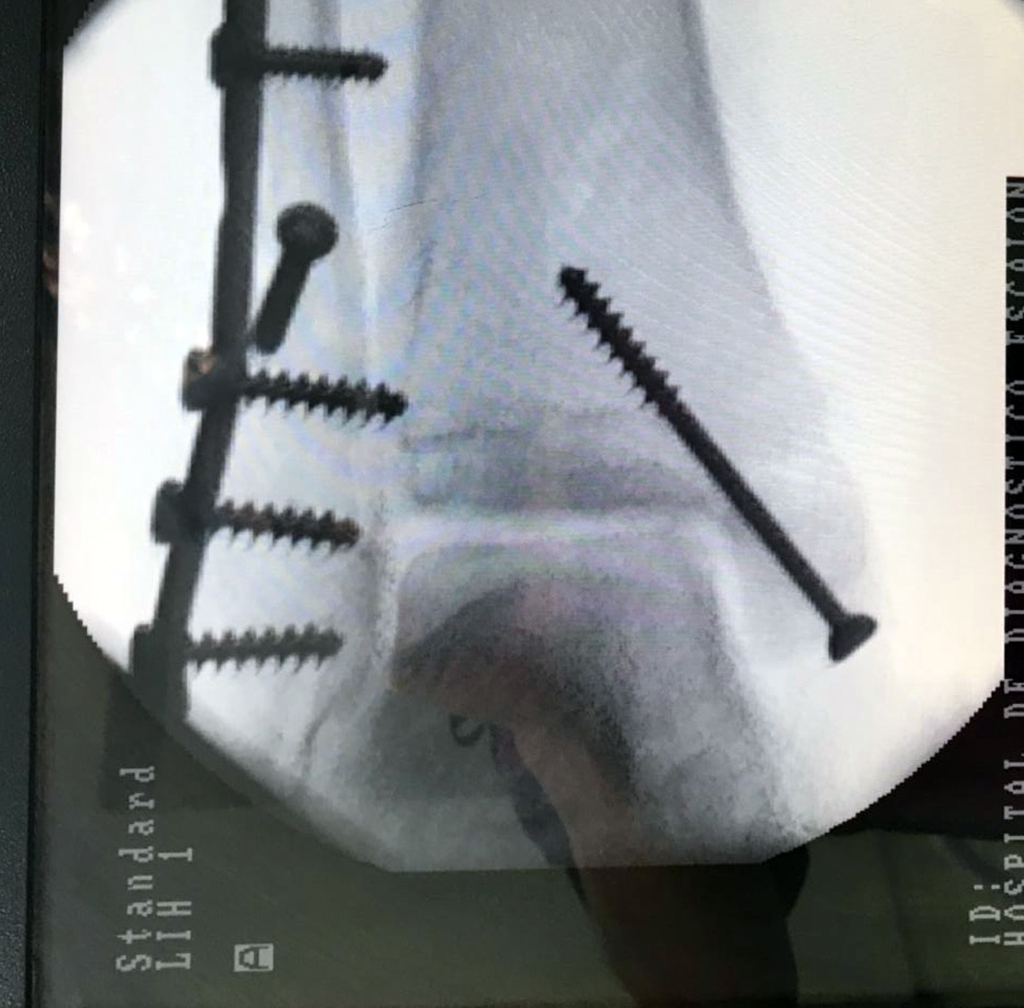

Cuando se necesita cirugía, es probable que esta implique el uso de clavijas de metal, tornillos o placas para sostener los huesos en su lugar mientras la fractura se consolida. Los elementos de soporte pueden ser temporales o permanentes.

Algunas fracturas de tobillo pueden requerir cirugía si:

- Los extremos de los huesos están desalineados entre sí (desplazados).

- La fractura se extiende hasta la articulación del tobillo (fractura intra-articular).